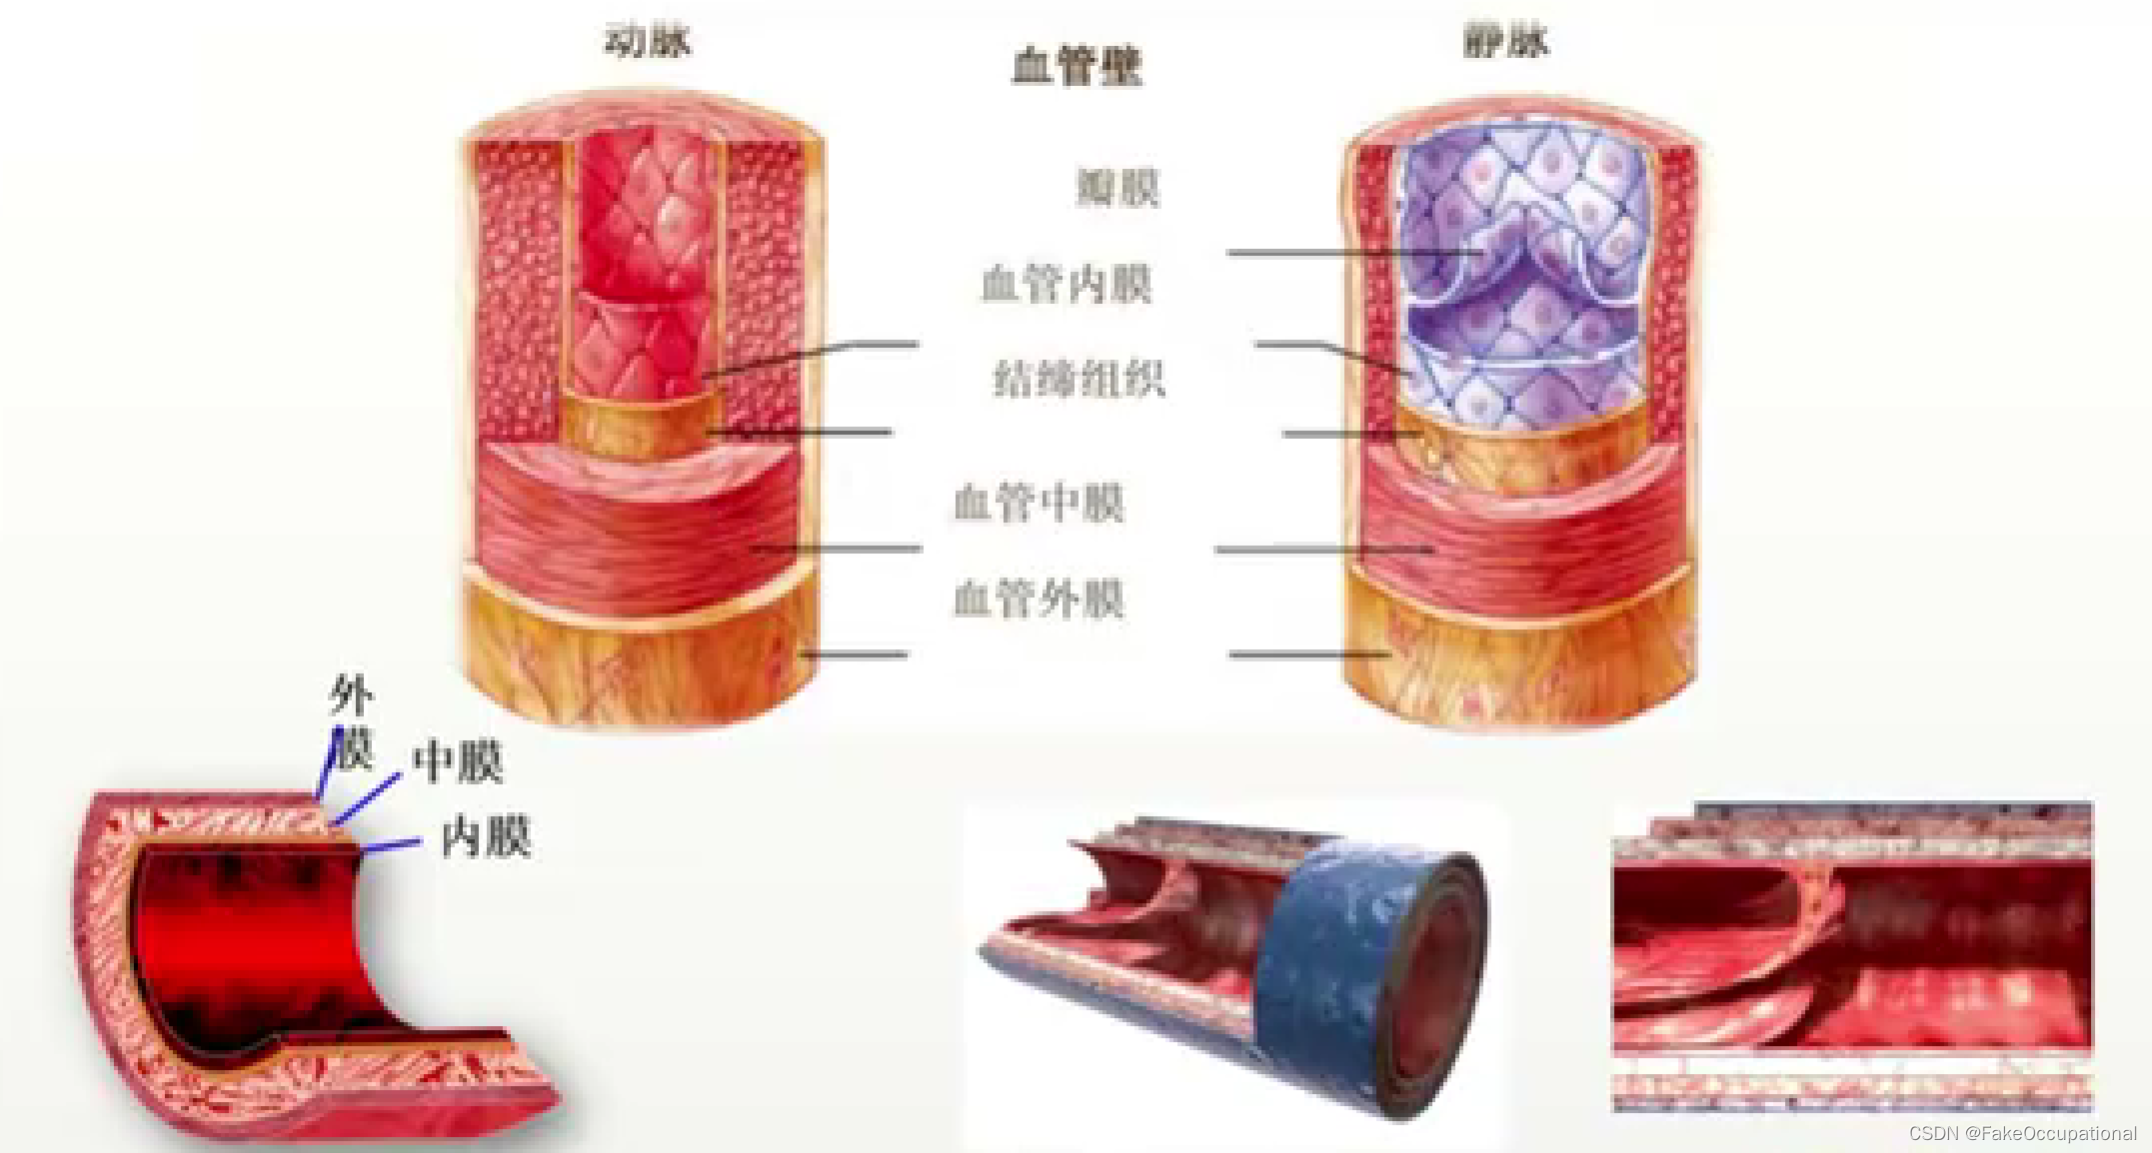

血管超声